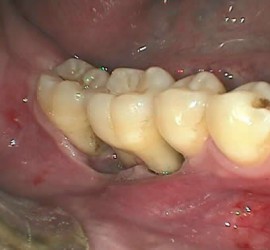

Аномалии строения и пороки развития зубов Пороки тканей зуба многообразны, они могут проявляться изолированно и сочетаться с аномалиями строения и пороками развития органов и систем всего детского организма, в том числе челюстно-лицевой области. Ткани зуба имеют эктодермальное (эмаль) и мезодермальное (дентин, пульпа, цемент) происхождение. В связи с этим пороки эмали […]